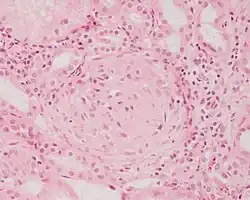

Photomicrograph of a kidney biopsy from a person with crescentic glomerulonephritis showing prominent fibrocellular crescent formation and moderate mesangial proliferation in a glomerulus. Hematoxylin and eosin stain.

Crescentic glomerulonephritis induced by infective endocarditis on PAS staining and immunofluorescence. PAS staining (left) demonstrated circumferential and cellular crescent formation with interstitial nephritis. Immunofluorescence (right) demonstrated C3 positive staining in mesangial area.

Photomicrograph of renal biopsy showing crescent formation and tuft narrowing. Periodic acid silver methenamine stain.

Rapidly progressive glomerulonephritis, also known as crescentic GN, is characterised by a rapid, progressive deterioration in kidney function. People with rapidly progressive glomerulonephritis may present with a nephritic syndrome. In management, steroid therapy is sometimes used, although the prognosis remains poor.[9] Three main subtypes are recognised:[4]: 557–558

Histopathologically, the majority of glomeruli present "crescents". Formation of crescents is initiated by passage of fibrin into the Bowman space as a result of increased permeability of glomerular basement membrane. Fibrin stimulates the proliferation of endothelial cells of Bowman capsule, and an influx of monocytes. Rapid growing and fibrosis of crescents compresses the capillary loops and decreases the Bowman space, which leads to kidney failure within weeks or months.